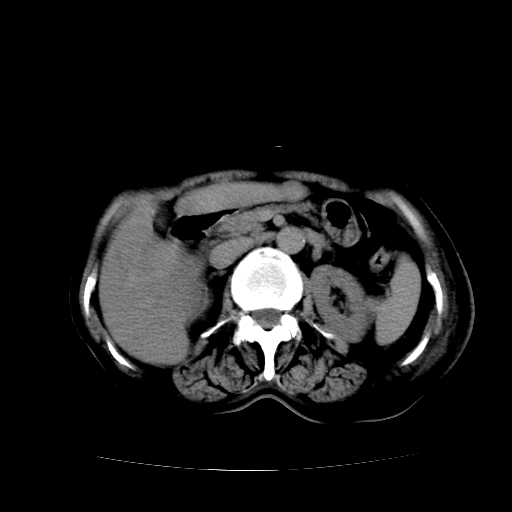

标题: CT17152:女70Y乳腺CA

女70y乳腺ca(针吸活检)

多部位转移瘤的诊断可以肯定,我的疑问是:双肺对称高密度影及胸水是否为心衰肺水肿,病人体虚弱,不好意思图象传的乱![em9]

肺部病变为淋巴转移,肝脏转移,及局部淋巴转移。胸水可能为淋巴回流受阻(血性的考虑胸膜转移)

癌性淋巴管炎,肝脏转移,瓷胆囊

1)左侧乳腺癌并左侧腋窝及纵隔淋巴结转移,两肺淋巴道转移(癌性淋巴管炎),肝脏多发性转移。2)双侧胸腔积液。3)慢性胆囊炎。